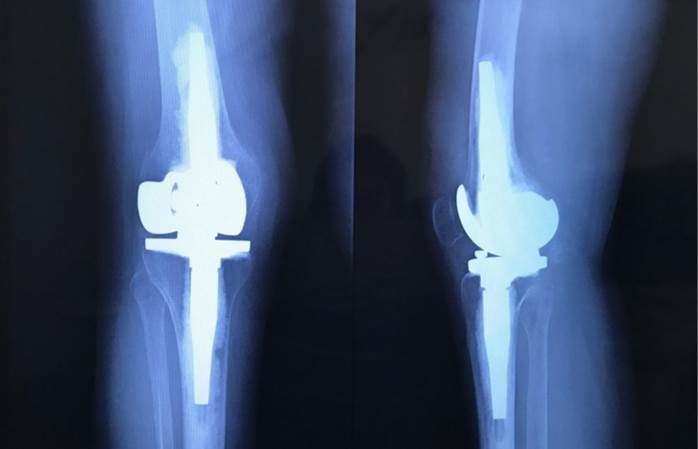

La posición cuasi invariable de flexión de la articulación de la rodilla de 9 ° durante el contacto inicial, la respuesta a la carga, el apoyo medio y el terminal, se corresponde con la valoración articular del rango de movimiento pasivo de rodilla, cuyo límite hacia la extensión es de - 9 °. Se puede observar, además, que la vista sagital de la radiografía postquirúrgica (Figura 2) muestra una prótesis en extensión completa, mientras que la posición de la articulación no se corresponde con la misma, y sí con un flexo de rodilla de 9 °. Esto podría deberse al reto técnico que supone una ATR en pacientes con secuelas de poliomielitis en los que generalmente se presentan, como se mencionó anteriormente, deformidades articulares y metafisarias, aumentada rotación tibial externa, valgos excesivo, pobre calidad del hueso, genu-recurvatum y laxitud ligamentosa, características que pueden alterar los procesos intrínsecos de la cirugía, como la realización de los canales para los vástagos tibial y femoral (1-2). También así la colocación adecuada de dichos vástagos y el fraguado del cemento, que al tratarse habitualmente de huesos osteopénicos, puede generar con facilidad alteraciones no deseadas en la alineación del el elemento protésico (8).